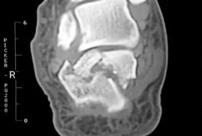

跟骨骨折冠状面影像

当跌倒后出现足后跟剧烈疼痛,局部肿胀及瘀斑明显,跟骨压痛,无法下地行走,应高度怀疑跟骨骨折,要马上到医院确诊(拍X光片,跟骨正侧位+轴位片)。对于严重的粉碎性或者波及关节面的骨折,最好还要做个CT,指导具体手术方案。

骨折严重者,需要经过手术钢板固定,将碎成几块的骨头,『拼合』起来固定。跟骨骨折的复位要求较高,要恢复关节与各关节面间的正常解剖关系(就是各归各位,保持正确的间距),同时,满足负重力线的种种要求。这样才能最大限度地减少创伤性关节炎的发生。